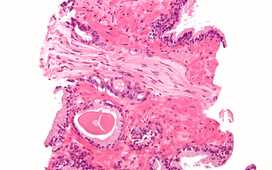

Ткани, полученные в результате биопсии, изучаются под микроскопом, окрашиваются специальными красителями (т. е. проводят гистологическое исследование), что позволяет установить не только сам факт наличия онкологического процесса, но и агрессивность опухолевого процесса. Пробы ткани предстательной железы дают важнейшую информацию для диагностики, стадирования заболевания, подбора адекватной тактики лечения и главное – определения прогноза для выживаемости пациента.